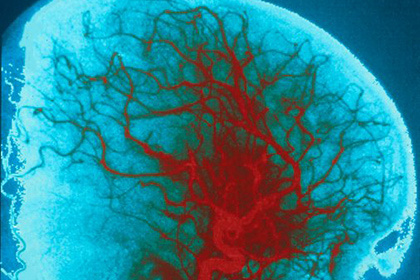

Международная группа ученых при участии исследователей из МГУ разработала конструкции, которые могут использоваться для стимуляции роста сосудов в тканях, пораженных ишемией. Свою статью они опубликовали в журнале Stem Cell Research and Therapy.

Тканеинженерные конструкции — так называемые «клеточные пласты», с помощью которых возможна стимуляция роста сосудов и регенеративных процессов в тканях, страдающих от ишемии. Такой способ доставки более эффективен, чем простая инъекция за счет повышения выживаемости. Более того, было показано, что при использовании клеток, обработанных вирусом с целью увеличения продукции фактора роста эндотелия сосудов (VEGF165), ангиогенный ответ и регенерация ткани могут быть усилены в еще большей степени. Из результатов работы был сделан вывод о возможности разработки нового метода регенеративной медицины, основанного на использовании клеточных пластов как эффективного биоматериала, не содержащего синтетических и ксеногенных компонентов".